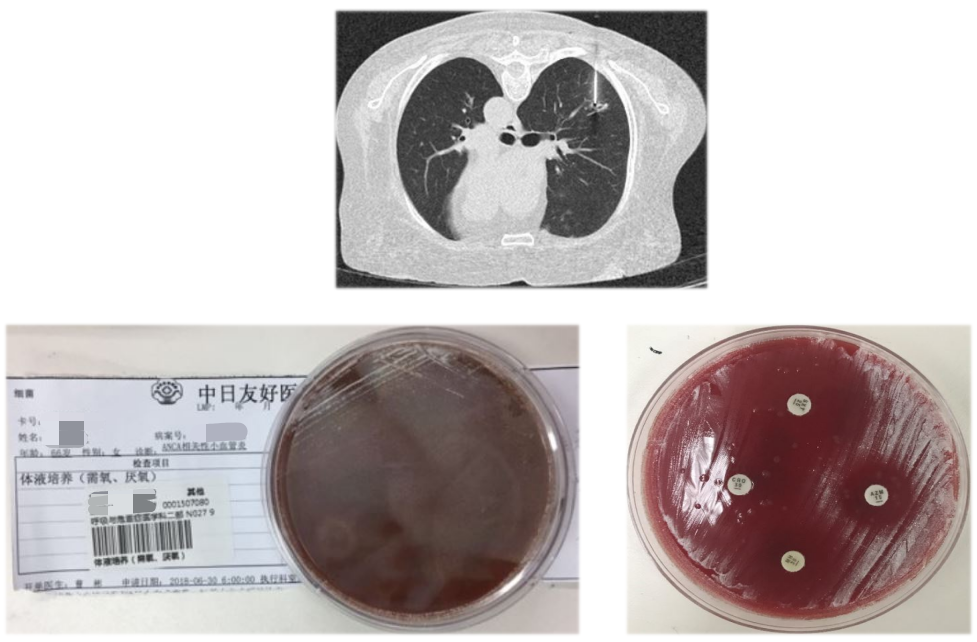

胸部CT显示只有一些小结节,播散性结节的可能。

经验告诉我们,这样的急性眼内化脓性感染要警惕其他部位脓肿播散。最常见的部位是肝肾脓肿,最常见病原体是肺炎克雷伯菌,最常见药敏为高毒力不耐药的肺炎克雷伯菌,最好的处置办法是「引流霉素」+敏感抗菌药物。

病人在没有肝肾功能异常的情况下,行腹部CT示明显的肝脓肿,我们进行了积极的穿刺引流,再加上抗生素治疗后,明确感染。

血培养、分泌物培养——肺炎克雷伯菌

明确为高毒力的肺炎克雷伯菌感染。

眼脓肿穿刺引流

每日眼科消毒换药2次。病原学方面血培养、眼部分泌物、肝脓肿培养均为肺炎克雷伯杆菌,先后给予敏感抗生素美罗培南(5天)、哌拉西林他唑巴坦(10天)感染治疗。

胸部CT(2017-11-8)

肺内结节得到好转吸收。经治疗后患者眼部症状逐渐减轻,眼部外形恢复正常,但遗留失明。